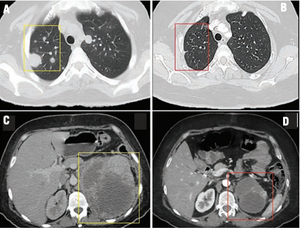

In this installement of Clinical Quandaries, Abigail Mateos-Soria, MD, and colleagues present a case of an 38-year-old woman who has a 3-month history of fatigue, dyspnea, significant weight loss, and severe left flank pain.